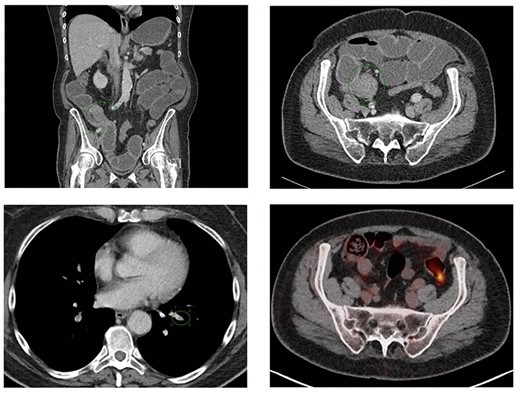

The following day, she underwent inferior vena cava filter (VCF) placement after which a right-sided hemicolectomy and creation of an end ileostomy were performed. During surgery, there was an abnormal tissue spot on the peritoneum, which was suspect for a metastasis. After complete abdominal cavity evaluation, the peritoneal carcinomatosis index was judged to be 2. Pathological examinations revealed stenoses in the terminal ileum and the cecum, caused by multiple loci of metastases of lobular breast carcinoma (Fig. 3) and peritoneal carcinomatosis. Resection margins were free from tumor cells, and there was no metastasis in 15 lymph nodes and omentum.

Macroscopic findings (A): in the longitudinal section of the cecum, there was no mucosal ulceration found. In the terminal ileum a stenosis was observed due to a submucosal circular pale mass. In the colonic wall and mesocolon, a hard pale mass was found too. Microscopic examination of the terminal ileum (B) and colon (C) showed that the mucosal layer was intact. The tumor cells with linear growth and loss of cohesion (D) were spread from the serosal to the submucosal layer (hematoxylin and eosin staining). Black bar indicates 500, 200 and 50 μm for Fig. 3B–D, respectively. The unexpected histological finding with lobular features, similar to the oncoplastic breast-conserving surgery specimen of the left breast, prompted further immunohistochemical study. In both the terminal ileum and in the cecum, the tumor cells were strongly positive for cytokeratin 7 (CK7), GATA-3 and estrogen receptor (ER). The tumor cells were negative for HER2 and progesterone receptor (PR) (similar to the pattern found in in the breast tumor). The markers of enteric differentiation: cytokeratin 20 (CK20), CDX-2 and carcinoembryonic antigen (CEA) were all negative. The positive staining of GATA-3, ER and CK7 is highly consistent with metastatic disease from the primary breast carcinoma.